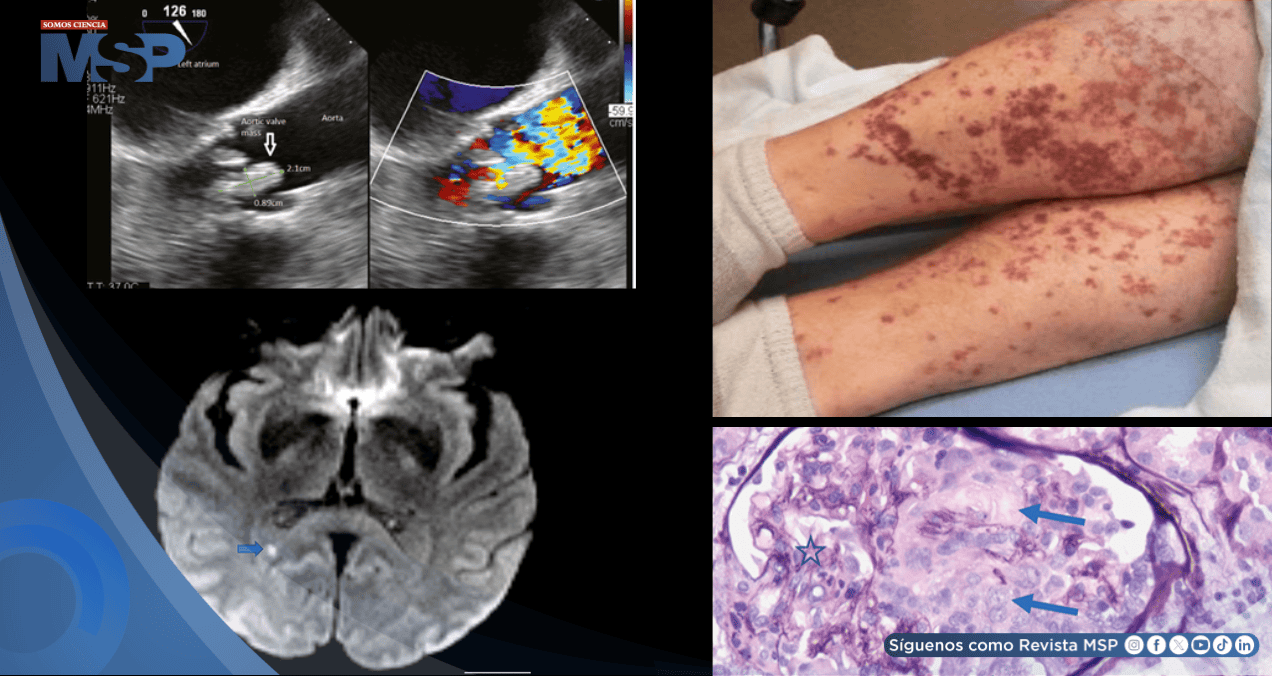

Un hallazgo significativo en las extremidades inferiores fueron lesiones purpúricas palpables bilaterales que no palidecían a la presión, afectando principalmente a sus espinillas. Se observó una fuerza motora disminuida, con 3/5 en la extremidad inferior derecha, mientras que la sensibilidad permanecía intacta y el signo de Babinski fue negativo.

Ante este deterioro clínico, se realizó una punción lumbar que resultó negativa para infecciones víricas, bacterianas o fúngicas. Una nueva resonancia magnética cerebral evidenció dos nuevas áreas de isquemia aguda, de aproximadamente 3 mm, localizadas en la sustancia blanca parietal izquierda y el cuerpo calloso posterior, sugiriendo eventos embólicos recurrentes.

Los hemocultivos obtenidos al ingreso dieron positivo para Lactobacillus acidophilus, confirmando la etiología de la infección. El ecocardiograma transesofágico realizado posteriormente mostró una válvula aórtica parcialmente calcificada con insuficiencia aórtica grave y estenosis aórtica leve, evidenciando además la presencia de vegetaciones compatibles con endocarditis.

Para establecer un diagnóstico definitivo de la afectación renal, se realizó una biopsia renal que mostró 22 glomérulos por sección de tejido, cuatro de los cuales presentaban necrosis fibrinoide segmentaria, restos cariorrecticos segmentarios y semilunas celulares. No se identificó hipercelularidad endocapilar glomerular.

La inmunofluorescencia fue negativa, estableciéndose el diagnóstico de glomerulonefritis necrosante focal pauciinmune, una entidad caracterizada por la ausencia de depósitos inmunes y asociada frecuentemente con vasculitis ANCA.